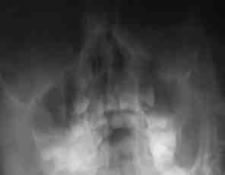

副鼻腔の炎症を診断するには顔のレントゲン検査をいたします。副鼻腔の粘膜はアレルギーの関与が大きいほど肥厚しています。治療には1ヶ月以上かかることもしばしばありますが子供のうちのしっかりと治しておけば、成人に持ち越すことはありません。

抗アレルギー剤の投与を併用します。また採血でアレルゲン(アレルギーの原因物質)を同定して予防していただくことも重要です。 レントゲンにて副鼻腔の病変が消失するまで行います。

▲治療後2ヶ月 -